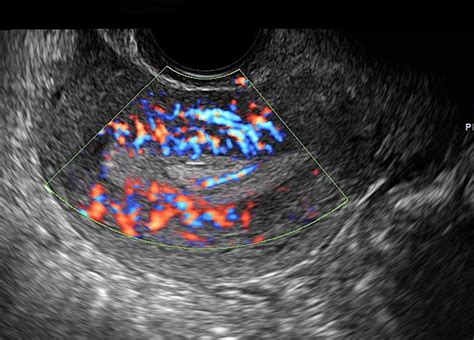

When it comes to gynecologic ultrasounds , there isn’t just one way to do things. Doctors typically choose the method that will give them the best view of the area they’re concerned about. The two main types are transabdominal ultrasound and transvaginal ultrasound . Let’s break them down. The transabdominal ultrasound is probably the one most people picture. Here, the technician applies a gel to your lower abdomen and then moves a transducer (the wand-like device) over the skin. This method provides a broader view of the pelvic organs and is often used when you have a fuller bladder, which helps push the organs up and away from the pelvic bone, making them easier to see. It’s great for getting an overall look at the uterus and ovaries, especially if there’s a concern about a large mass. Now, the transvaginal ultrasound is a bit different and often provides more detailed images of the uterus and ovaries. For this type, a smaller, covered transducer is gently inserted into the vagina. Don’t worry, guys, it’s usually not painful, just a bit strange feeling for some. This method allows the sound waves to get closer to the organs, resulting in clearer, more magnified images. It’s particularly useful for examining the uterine lining, detecting small fibroids or cysts, and evaluating early pregnancy. Sometimes, your doctor might recommend a combination of both to get the most comprehensive information. There’s also a specialized type called a 3D ultrasound , which can create more realistic, three-dimensional images of the pelvic organs. This can be helpful in diagnosing certain congenital abnormalities of the uterus or providing more detailed views of fibroids. Finally, there’s the Doppler ultrasound , which is often used in conjunction with other types. This technique assesses blood flow within the pelvic organs, which can be important in evaluating conditions like ovarian torsion or assessing blood supply to tumors. Each type has its strengths, and your healthcare provider will select the best approach for your specific needs.